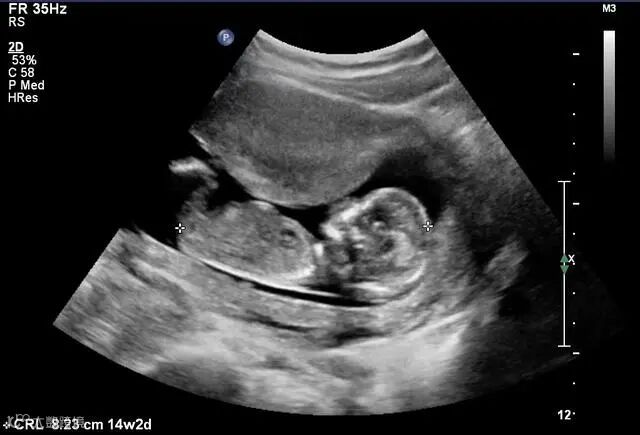

1.医学领域超声:超声波是一种特殊类的声波,人耳虽然听不到,但是利用超声波对人体进行检查,探查人体内部器官,骨骼结构是否正常。

人体生命检测“B超”